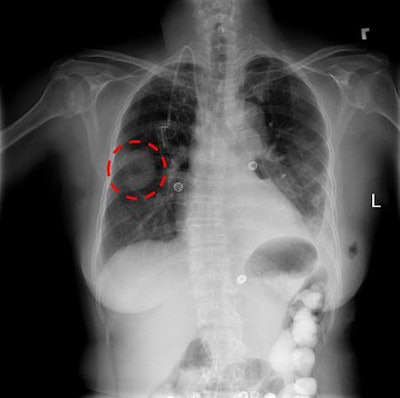

The database was created from studies of 30,000 patients who were seen at the NIH Clinical Center in Bethesda, MD; the information has been anonymized to protect patient identities. A number of the images are of patients with advanced lung disease, according to the NIH. The NIH Clinical Center is the country's largest hospital devoted entirely to clinical research, and patients who are seen there voluntarily agree to participate in clinical trials.

The NIH noted that interpreting a chest x-ray is a complex reasoning problem that "often requires careful observation and knowledge of anatomical principles, physiology, and pathology." These factors can make it more difficult to develop a consistent and automated technique for interpreting chest x-rays while also considering all possible thoracic diseases.